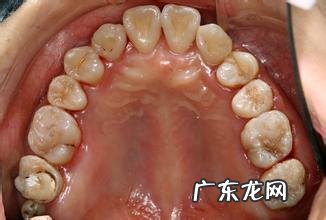

3、患牙列拥挤

口腔环境不合适是导致种植牙失败的重要原因 。一般来说 , 患者的牙列拥挤 , 是造成种植牙失败的重要原因之一 。因此 , 我们在进行种植牙之前需要检查自己所患牙是否存在拥挤 , 并进行矫正 。如果你感觉自己的牙齿比较拥挤 , 那么你必须得到更多的关注 。因为你的牙齿已经是拥挤得很严重了 。为了保证牙齿正常咀嚼功能 , 种植牙不应该暴露出来 。牙列拥挤是非常严重的身体疾病需要及时处理 。这就是为什么人们认为种植牙会导致严重拥挤的原因之一 。